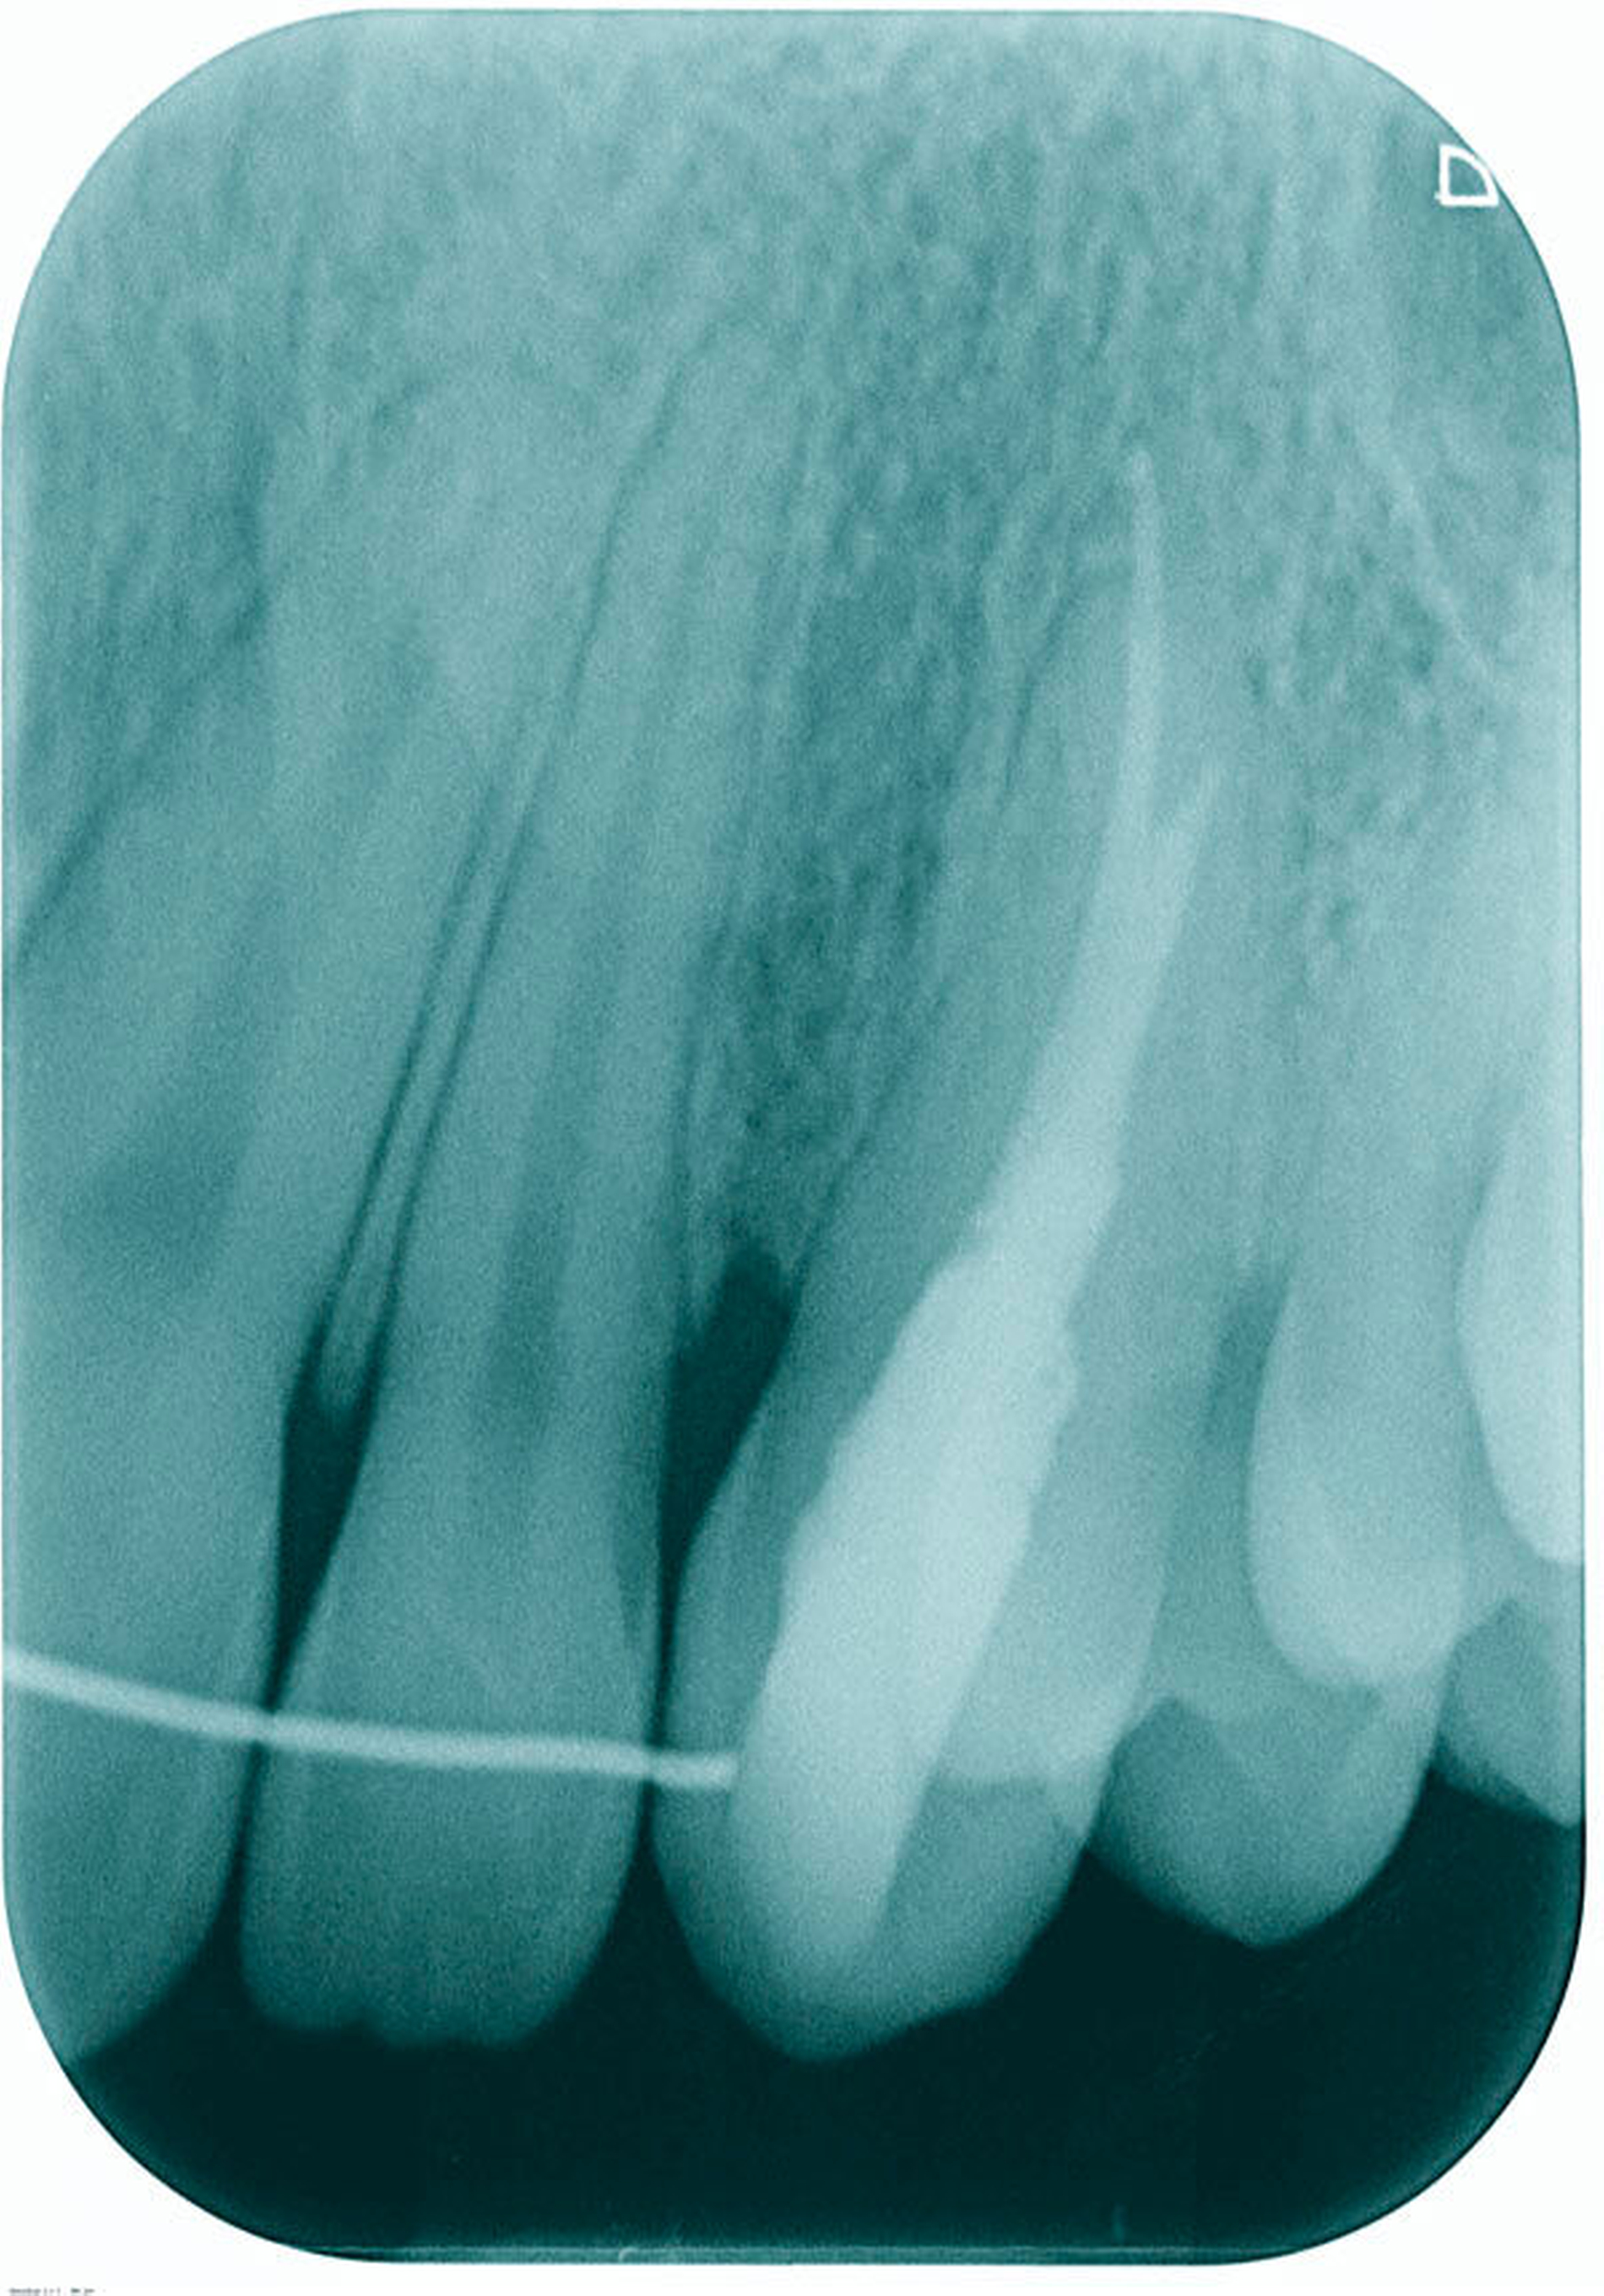

Es erfolgte die Inspektion unter dem OP-Mikroskop. Klinisch zeigte sich kein Anhalt auf Kanalstrukturen. Es erfolgten zwei zeitintensive Sitzungen, in denen der Wurzelkanal nicht dargestellt werden konnte und der Zahn, trotz größter Vorsicht und Verwendung des Mikroskops, perforiert wurde. Die Perforation war vestibulär im mittleren Kanaldrittel nach einer Länge von 18 mm lokalisiert (Abbildungen 3 und 4). Die Therapieentscheidung fiel daraufhin zugunsten einer „Guided Endodontics“-Behandlung.

In der folgenden Sitzung wurde die Schiene angepasst (Abbildung 10), die Trepanationsöffnung ergänzt und die Bohrung mittels Endoseal-Bohrer auf die zuvor am DVT geplante Tiefe vorgenommen. Nach erfolgter Bohrung wurde der Kofferdam angebracht und das erschlossene Kanalsystem mit einer ISO 10 C-Feile sondiert (Abbildung 11). Die Endometrie ergab 23,5 mm. Eine Röntgenkontrastaufnahme mit einer ISO 15 K-Feile wurde angefertigt (Abbildung 12). Die mechanische Wurzelkanalpräparation erfolgte mit Reciproc Blue 25 und 40 (VDW, München), die Desinfektion mit NaOCl 5 Prozent und EDTA 17 Prozent. Die Perforation wurde mit Total Fill BC Root Repair Material (FKG, La Chaux-de-Fonds, Schweiz) abgedeckt (Abbildung 13). Im Anschluss wurde eine Masterpointaufnahme angefertigt (Abbildung 14), der Wurzelkanal mit Total Fill BC Points und Sealer (FKG, La Chaux-de-Fonds, Schweiz) biokeramisch abgefüllt (Abbildung 15) und adhäsiv verschlossen. Bei der klinischen Nachuntersuchung nach vier Wochen war der Zahn symptomlos.